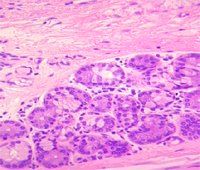

定義:口腔、胃、腸等消化道、呼吸道、尿道等 器官裡面的一層薄膜,內有 血管和 神經,能 分泌黏液。消化道最裡面的一層是叫做黏膜的東西。它被分為三個部分。